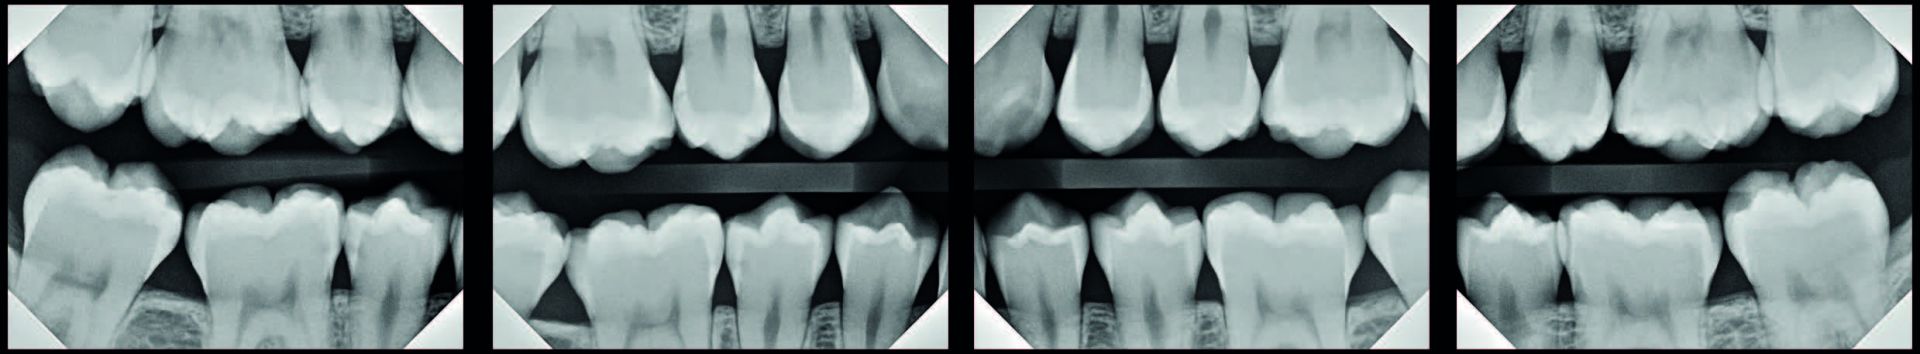

The way I was taught to treat class II lesions is antiquated, unpredictable, and barbaric. Take a look at the bitewings in [Figure 1].

If you are anything like me, you would have recommended some watches, and some class II fillings. That’s what I did for over 20 years. And I now really regret it. Sadly, for a variety of reasons, neither is a great option. First, drilling is barbaric, destructive, and incredibly invasive. Let’s zoom in on the anterior right radiograph [Figure 2].

More than likely, the majority of you believe that #4, #29, #30 and #31 require some kind of intervention. At the very least, they shouldn’t be completely ignored. If you received your dental training similar to mine (I graduated from the University of Michigan in 2004), then it is within the realm of possibility that you would recommend quite a few MOs and DOs, maybe even an MOD for #30.